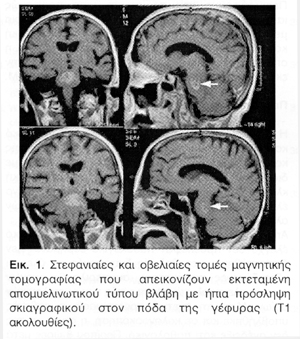

Από τον βασικό εργαστηριακό και παρακλινικό έλεγχο δεν προέκυψαν παθολογικά ευρήματα. Δεν διαπιστώθηκαν μεταβολικές διαταραχές και όλες οι εξεταζόμενες παράμετροι, συμπεριλαμβανομένων και των ηλεκτρολυτών, ήταν εντός των φυσιολογικών ορίων. Μετά τη σχετική προετοιμασία η ασθενής υποβλήθηκε και σε κολονοσκόπηση, η οποία επίσης δεν ανέδειξε κάτι παθολογικό. Περίπου 8 ώρες μετά την ολοκλήρωση της κολονοσκόπησης κι ενώ η ασθενής είχε επιστρέψει χωρίς προβλήματα από το ενδοσκοπικό εργαστήριο στο θάλαμο νοσηλείας παρουσίασε συγχυτικοδιεγερτική κατάσταση και στη συνέχεια βαθμιαία επιδεινούμενη στένωση συνειδησιακού επιπέδου για να καταλήξει σε σχεδόν κωματώδη κατάσταση (Κλίμακα Γλασκόβης 6) αντιδρώντας μόνο σε επώδυνα ερεθίσματα. Από τις πληροφορίες που έδωσαν οι συγγενείς της πιθανολογείται το ενδεχόμενο να παρουσίασε επίσης γενικευμένη τονικοκλονική επιληπτική κρίση. H αξονική τομογραφία εγκεφάλου που έγινε επειγόντως απέκλεισε το ενδεχόμενο ενδοεγκεφαλικής αιμορραγίας, άλλης χωροκατακτητικής βλάβης ή γενικευμένου εγκεφαλικού οιδήματος. H ασθενής μεταφέρθηκε στη μονάδα εντατικής θεραπείας για παρακολούθηση και περαιτέρω αντιμετώπιση. Η ασθενής μετά την πάροδο 24 ωρών επανέκτησε πλήρη επαφή με το περιβάλλον. Παρουσίασε όμως δυσκαταποσία, δυσαρθρία και βαρύτατη κορμική αταξία αδυνατώντας ακόμη και να καθίσει χωρίς υποστήριξη. Η μαγνητική τομογραφία εγκεφάλου που ακολούθησε ανέδειξε μια εκτεταμένη βλάβη στην περιοχή του πόδα της γέφυρας χωρίς περιεστιακό οίδημα και μέτριας έντασης πρόσληψη παραμαγνητικού σκιαγραφικού στα όρια της βλάβης (Εικόνα 1). Διαφοροροδιαγνώστικα τέθηκε αρχικά το ερώτημα ισχαιμικού εμφράκτου ή πρωτοπαθούς όγκου του εγκεφαλικού στελέχους και συνεστήθη επανάληψη του απεικονιστικού ελέγχου μετά την πάροδο δύο εβδομάδων. Στη φάση αυτή αποφασίστηκε από τους θεράποντες ιατρούς η ενδοφλέβια χορήγηση κορτικοστεροειδών, υπό την έννοια της προληπτικής αποιδηματικής αγωγής. H ασθενής παρέμεινε ουσιαστικά σταθερή και μεταφέρθηκε στον κανονικό θάλαμο νοσηλείας. Στη συνέχεια παρουσίασε ηπιότατη κλινική βελτίωση και συνέχισε τη λήψη κορτικοστεροειδών από το στόμα. Στο σημείο αυτό ζητήθηκε νευρολογική κλινική εκτίμηση της ασθενούς.

Από τη μελέτη του ιατρικού φακέλου της ασθενούς διαπιστώθηκε ότι η ασθενής κατά την οξεία εγκατάσταση των συμπτωμάτων της τρεις εβδομάδες νωρίτερα και μόλις 8 ώρες μετά την ολοκλήρωση της κολονοσκόπησης είχε παρουσιάσει βαρύτατη υπονατριαιμία (108 mmol/Ι), αν και κατά την εισαγωγή της μόλις ένα 24ωρο νωρίτερα είχε απόλυτα φυσιολογικές τιμές νατρίου. Λαμβάνοντας υπόψη τη λήψη διουρητικών για την αντιμετώπιση της αρτηριακής υπέρτασης, της κακής διατροφής της ασθενούς λόγω της καταθλιπτικής της συνδρομής και των πρόσφατων κοιλιακών της ενοχλημάτων, αλλά κυρίως τη χορήγηση καθαρτικών για την προετοιμασία της προγραμματισμένης κολονοσκόπησης το εύρημα αυτό βρήκε την ερμηνεία του. Όπως προέκυψε από τα εργαστηριακά των αμέσως επόμενων ωρών η επαναφορά των επιπέδων νατρίου εντός των φυσιολογικών ορίων (132 mmol/Ι) επιτεύχθηκε εντός μόλις 12 ωρών με ταχύτητα διόρθωσης της τάξης των 2 mmol/Ι ανά ώρα. Ως εκ τούτου ετέθη άμεσα η υπόνοια ότι πρόκειται περί εντοπισμένης στη γέφυρα απομυελινωτικής βλάβης στα πλαίσια ιατρογενούς κεντρικής γεφυρικής μυελινόλυσης, και όχι περί ισχαιμικού εμφράκτου ή νεοπλασίας. Με βάση το σκεπτικό αυτό ζητήθηκε η άποψη έμπειρου νευροακτινολόγου, ο οποίος κατηγορηματικά απέκλεισε κάθε ενδεχόμενο ισχαιμίας ή όγκου τεκμηριώνοντας με δεδομένα τα απεικονιστικά χαρακτηριστικά της βλάβης (εστία μειωμένης έντασης σήματος με ήπια πρόσληψη σκιαγραφικού στις Τ1 και αυξημένης έντασης σήματος στις Τ2 ακολουθίες (Εικόνα 2), έλλειψη περιεστιακού οιδήματος) την απομυελινωτική αρχή της βλάβης στα πλαίσια "οσμωτικού απομυελινωτικού συνδρόμου". Η επανάληψη της μαγνητικής τομογραφίας με την επιπλέον λήψη ακολουθιών διάχυσης (DWI) και μεταφοράς μαγνητισμού (magnetisation transfer) επιβεβαίωσε την ως άνω διάγνωση.